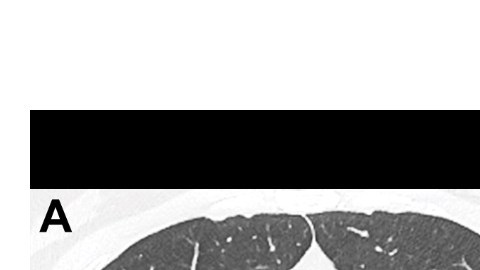

Así lucen los pulmones de una paciente de coronavirus. Crédito: Radiology | Cortesía

Su tomografía computarizada reveló unos parches que se ven como vidrio esmerilado, o líquido en los espacios en los pulmones. Estos son indicios que se encuentran comúnmente en las radiografías de pacientes con casos graves.

Normalmente, a una persona no se le realizaría una exploración del tórax, como en el escenario, pero los médicos hicieron una excepción en su caso. Encontraron opacidad de vidrio esmerilado en sus pulmones, las marcas de la neumonía Covid-19.